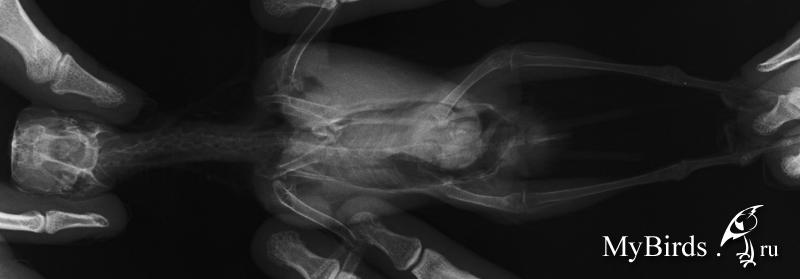

NikaK Опубликовано 9 сентября, 2013 #1 Опубликовано 9 сентября, 2013 (изменено) Розеллы мальчик и предположительно девочкамальчик - 11 лет, девочка год с небольшимрацион содержание и прочее - в темеhttp://www.mybirds.ru/forums/index.php?sho...&hl=розелла сейчас мне нужен только ответ по конкретным рентгенам. большие изображения лежат вот тут ftp://ftp.batteryteam.ru/pdf%20to%20print/Мальчик 11 лет Девочка (может быть нет) 1,5 года вопрос - можно ли по этим снимкам подозревать аспергиллёз?заранее спасибо за ответ. Изменено 9 сентября, 2013 пользователем NikaK

Zosia Опубликовано 9 сентября, 2013 #2 Опубликовано 9 сентября, 2013 У саммца (Жорка,да?) точно что-то есть, и одно легкое нехорошо вздуто. У самки если и есть (в центральной части затемнение)- видно плохо. Анализ нужно делать,причем 3 раза.Аспергиллез по трем анализам ставят,два должно быть положительно. Т.к. лечение его а)- дорогое (очень), б)- токсично, требует параллельно несколько препаратов- для прикрытия.

Zosia Опубликовано 10 сентября, 2013 #10 Опубликовано 10 сентября, 2013 Так.Поговорила с теми,кто вас сейчас ведет. Мое мнение- до аспергиллезного диагноза вам надо исключить ТУБЕРКУЛЕЗ,т.к. ваша упавшая иммунка, и то что на ваших птиц все садится, и то что одна птица явно заразилась от второй (а такого в ДОМАШНИХ условиях при аспергиллезе практически не бывает,зато бывает при туберкулезе) и специфически вздутое лоегкое, и сетчатый рисунок на нем- может говорить именно о Т, а не о А. исключить (или подтвердить) Т легче,чем А. Это сделают в Горветлаборатории.Я созвонилась с ними, и созвонилась в Мариной Лешковой (Центр, вы в четверг илите- будете сдавать кровьЮ смыв и,возможно,фекалии- на исключение туберкулеза. До результатов анализа- максимально птицу иммунить (всем чем можно- от катозала до фоспренила), только если прмиенять будете параллельно два иммуностимулятора- дозы давать половинные по каждому. А иммуномодулятор (деринат например) или иммунопротектор (катозал)- без изменений.Дозы "стандарт" по иммуностимуляторам: 0,02 мл на каждые полные 50 граммов веса птицы суточноИммуномодуляторы- 0,054 мл суточно на каждые 50 граммовиммунопротекторы- 1:200 в поилку.исключить все фрукты и овощи (ВРЕМЕННО).Никаких витаминов.

Zosia Опубликовано 10 сентября, 2013 #12 Опубликовано 10 сентября, 2013 тогда я правильно не начала давать назначенный орунгал Н.С. так там в четверг будет принимать Лешкова? А с Волгиной мне как объясниться?) Точно так же. Наталья Сергеевна сейчас на конференции в НовоСибе, но она будет в курсе. Я могу объяснитьна чем базируется мое мнение(как я М уже объяснила).1. Изначально была нездорова одна птица. Вторая заразилась от неё. При аспергиллезе такого в условиях квартиры или квартирного вольера не происходит (у вас же не капает по стенам,не ползет плесень по углам, не летает гуано и сопли-как на прицефермах). А вот туберкулез вполне воздушно-капельным путем даже в квартирных условиях мог передаться.2.Иммунка у вас упала уже полтора года как. На аспергиллезе птиц бы уже помер.На туберкулезе может жить долго- если постоянно поддерживать антибиотиками (даже непрофильными),иммуностимуляторами.3.У самца резко вздуто одно легкое- по клинике детей это характерно для туберкулеза. Хотя А тоже может такое дать(агрессивный), но опять же- птиц бы уже ушел за радугу.4.Мозаичный рисунок легких... 5.У самки по центру что-то.похожее на аспергилломы, виднеется.Но ровно так же это может быть и туберкулемы. Ответ даст только анализ. На анализ будет взята кровь,мазок,помет.Проводить будут в Горветлаборатории (ул.Юннатов 16 а), я с ними созвонилась уже. В принципе можно было бы обойтисьь гораздо меньшими проблемами, если бы была туберкулиновая проба.НО! Нет сейчас в Москве малых фасовок птичьего пробника,только по 38 кг (на птицефермах), а отщипнуть не дают. А так- можно было бы поцарапать кожу,нанести пробу и посмотреть результат. Хотя конечно бывают наверное какие-то варианты аспергилл, нетипичные, малоагрессивные, при этом высокоустойчивые к внешним факторам и передающиеся прямо по сухому воздуху московских квартир (26,30% влажности в отопительный сезон). Как известно,только гильотина дает 100% однозначный результат.если будет туб- его лечить уже чисто антибиотиками.с прикрытием системными антмикотиками. лечат долго, но хоть уверенно.

NikaK Опубликовано 12 сентября, 2013 Автор #18 Опубликовано 12 сентября, 2013 (изменено) Так, была на приеме, взяли кровь, дали две пробирки для помета. Но...позвонита в горвет на юннатов - они сказали, что:1. анализ ТАКОЙ можно сдавать ТОЛЬКО при направление наблюдающего врача...они конечно не откажут взять, но типа это на них вешается ответственность лишняя, и им это не очень то хочется. сказали под паспортные данные - ок, фиг с ними.2. КРОВЬ - НЕ берут на туберкулез... берут смыв из глотки, помет, и что-то еше, я от удивления забыла. Получается что у меня только 1 из 3 анализов... достоверность видимо равна ....и еще посмотрели еще пристально Н.С. и Мария рентген обоих - приказывают лечить орунгалом (+ преднизолон для триши с полиурией, +пробиотик, +АЦЦ в поилку, +мовалис 2 недели, + иммунофан для обоих все кроме 1) ... я еще больше в растерянности... Изменено 12 сентября, 2013 пользователем NikaK

Zosia Опубликовано 15 сентября, 2013 #31 Опубликовано 15 сентября, 2013 сегодня второй день по вышеописанной схеме - ттт! - все вроде без проишествий... надеюсь и дальше так же будет. а аспергиллез- -так же, ничем 100% не подтверждается у живой птицы? Подтверждается, но не всегда.Кишечный- легко,легочный- очень трудно. Рентгеноскопически- при наличии аспергиллом явных (тут как раз обязательно дифференциировать от тубекулеза,т.к. он дает туберкуломы,похожие немного на аспергилломы).Вздутые легкие и мешки,наличие жидкости в них,тяжелое и мелкое дыхание, ослабленность,упавшая иммунка.Т.е. часть симптомов- косвенная и может быть неоднозначна.(Микоплазмоз напрмиер,который у вас исключали в первую очередь).

NikaK Опубликовано 10 ноября, 2013 Автор #36 Опубликовано 10 ноября, 2013 Продолжу тему.Пропили месяц все назначеное (орунгал, что там, пробиотик, иммуно стимулятор)после лечения спустя неделю опять повыпадали перья. Преимущественно хвост и подхвостье у Джека, красненькие снизу вообще три осталось. У Триши все разные, со всех мест. Так же у нее сохраняется полиурия и одышка в большой степени.Вот новые исследования. Ждем анализ на вирусы цирко- и еще какие -то 2(((